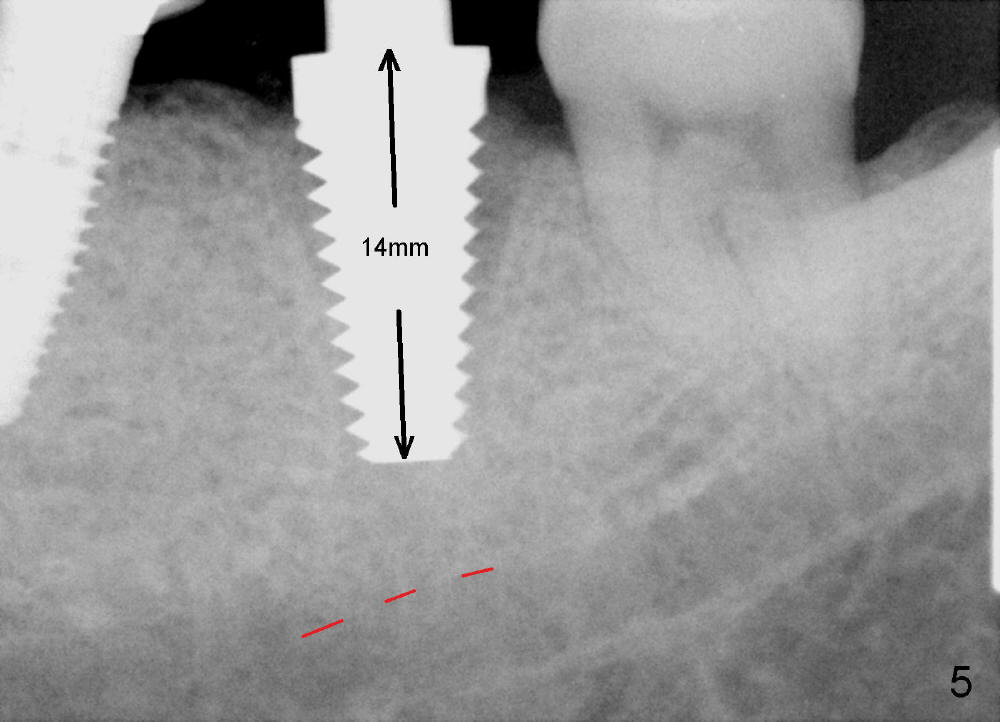

The septum of the socket is thin (Fig.3*), and easily removed, leaving a large socket. Osteotomy is initiated with 2 mm pilot drill in the middle of the socket, slightly mesiolingual, since the buccal and distal bone is low and defective. Reamers (2.5 to 4 mm in diameter) are sequentially used to enlarge osteotomy and harvest autogenous bone (Fig.4 (3 mm reamer in place). When 5 mm tap is placed, there is no stability. Six mm tap gains some stability, but the socket is not closed. Seven mm tap achieves strong stability and is closing the socket (Fig.5). Ultimately a 7x14 mm implant is placed with insertion torque more than 60 Ncm (Fig.6). The implant almost obliterates the socket (Fig.7). The harvested autogenous bone is placed in the buccal and distal aspects of the socket before Chromic gut suture (4-0) is placed distally. Fig.8,9 show the healing socket 6 days and 1.5 months postop, respectively. Osteointegration appears to occur in 2.5 months (Fig.10, compare to Fig.6). Bone level remains the same 1 year post cementation (Fig.11).